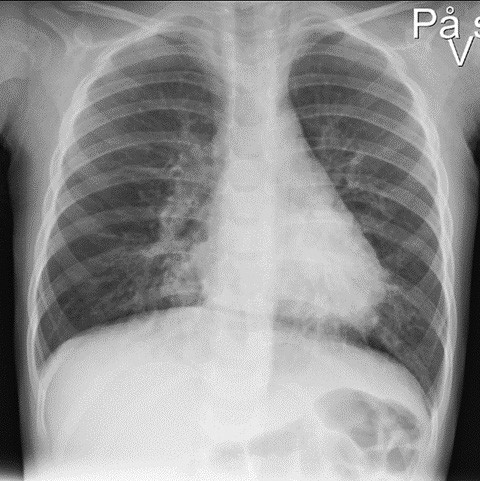

The condition was interpreted as pneumonia, and the patient was admitted to the paediatric ward. A total of 315 mg of penicillin was administered intravenously, and high-flow nasal cannula therapy was started at a rate of 15–25 litres per minute and 40 % oxygen supplementation. Inhalations with 3 ml NaCl and 2.5 mg of salbutamol had an uncertain effect. Chest X-ray showed perihilar opacities (Figure 1). After five hours, the child appeared more fatigued but was still aware of their surroundings. Breathing entailed wheezing with prolonged expiration. The duty paediatrician noted diminished breath sounds on the right side.

Most children who are evaluated for suspected foreign body aspiration undergo a chest X-ray (> 80 %), and 30–50 % of these are reported to have normal findings (3, 5). Our patient's X-ray showed signs of infection but no suspicion of a foreign body. Given the two-week history of coughing, it is possible, in hindsight, that the child may also have had a mild viral respiratory infection.